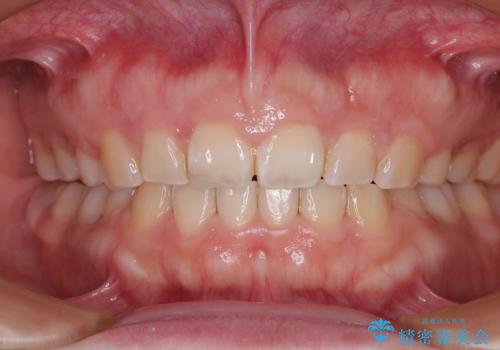

- 出っ歯と口の閉じにくさ、デコボコを気にして来院された患者様です。

口元の突出感を改善するため、上下左右第一小臼歯4本の抜歯を行い、ワイヤー装置による矯正治療を行うこととしました。

抜歯矯正を行ったことで、顎先のつっぱり感や口元の閉じにくさを解消することができました。